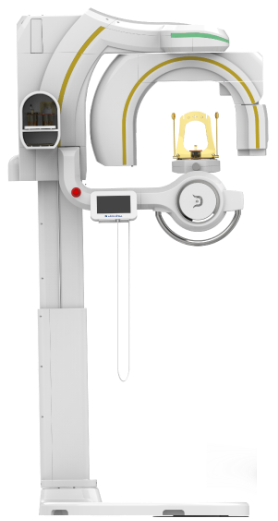

Dentri Max CBCT - from HDX Will (16x18) - Call for Special Pricing

- Products Model: PR.NDA30.100.01.00 PR.NDA30.100.01.01C PR.NDA30.100.01.01S

- Product Brand: HDX Will

- Condition: New

- Warranty: 5 Years

Introducing the Dentri Max, a game-changer in dental imaging tailored just for you! With its impressive Field of View (FOV) of 18 x 16.5cm, this model promises visually stunning images that redefine precision diagnostics.

Designed to cover a wide spectrum of dental needs, the Dentri Max is your all-in-one solution for endodontics, implantology, craniomaxillofacial, and cephalometric analysis. Say goodbye to blurry images and hello to crystal-clear clarity, thanks to its cutting-edge image-processing algorithm and metal artifact reduction technology.

But that's not all – the Dentri Max goes above and beyond with features like extraoral bite-wings, FMX from panoramic shots, 3D picture superimposition, and one-step airway analysis. It's like having a complete 2D/3D imaging package right at your fingertips, tailor-made for every aspect of your practice.